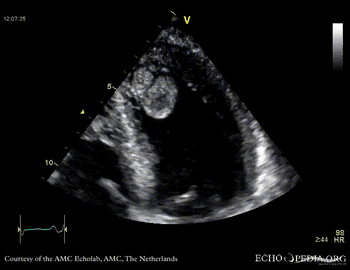

Thrombus in the left ventricle

J. Vleugels, AMC, The Netherlands